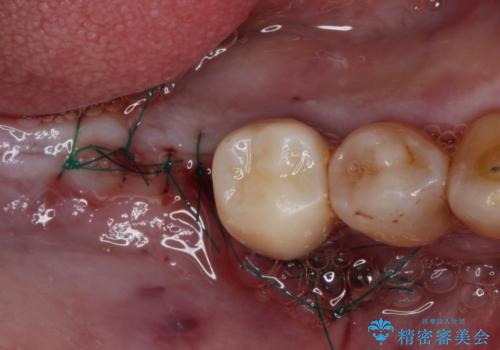

矯正治療を仕上げ、必要に応じて歯周外科処置を行い、適宜インプラントを埋入しながら咬み合わせを回復させていくこととしました。

治療前は磨き残しが多く見られ、全体的に歯肉が腫れている状態でしたが、抜歯の必要な歯を抜いたことで口腔内の環境が改善され、磨き残しも少なくなってきました。

インプラントにより咬合が回復したことで、治療開始時に認められた上顎前歯の動揺も改善されました。